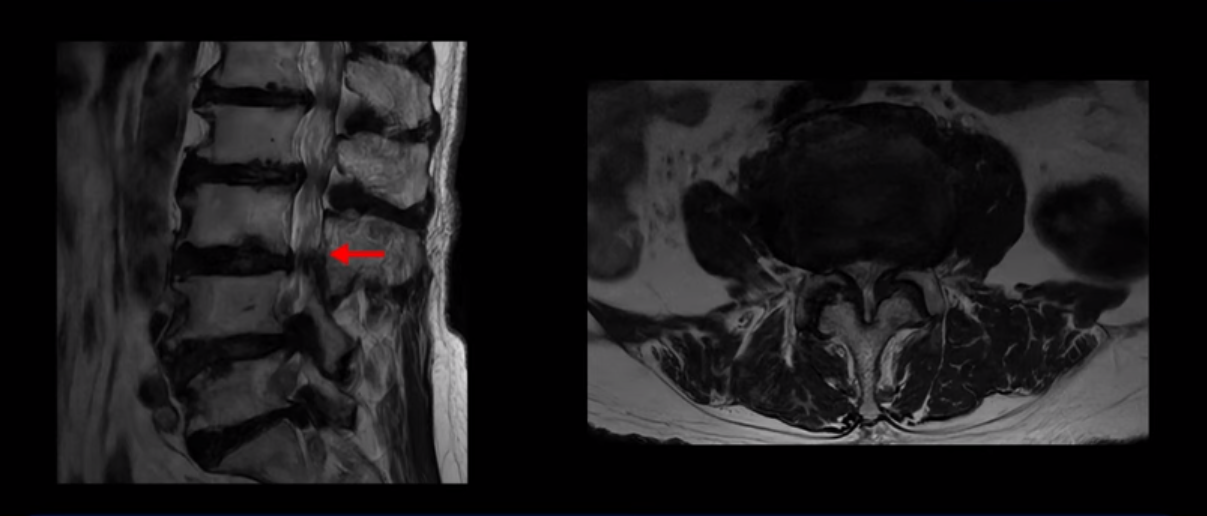

이 환자분은 MRI로 보면 허리 여러 마디가 신경이 매우 심하게 눌려 보이는 분입니다. 이분 MRI를 보면서 간단히 설명해 드린 후 어떻게 이렇게 신경이 심하게 눌린 환자분이 수술 없이 근육신경재활치료로 좋아질 수 있는지, 다리가 아파 걷지 못하는 환자가 어떻게 안 아프고 잘 걸을 수 있게 되는지, 10년 동안 괴로웠던 양 발의 시린 증상은 어떻게 사라질 수 있는지, 치료는 어떻게 하는지 자세히 설명 드리겠습니다.

MRI 보시면 (2-8) 허리의 5마디가 전부 다 심하게 퇴행되어 있습니다.

5마디 전부 다 심한 중심성 협착이 있습니다.

이렇게 모두 다 심하게 막히는 경우는 드문데요. 또한 오른쪽, 왼쪽 신경이 빠져나가는 추간공도 다 심하게 막혀있습니다.

오른쪽, 왼쪽 이렇게 신경 구멍들이 다 좁아지고 신경이 눌리니까 양쪽 다리가 발바닥까지 아파서 걷기 어렵고 양쪽 발이 10년 넘게 시린 겁니다. 당연히 수술해서 눌린 신경을 풀어줘야 한다고 들으셨는데요. 이런 환자분을 어떻게 수술 없이 치료할까요? 지금부터 설명해 드립니다.

이분 신경이 눌리는 증상은 오래됐지만, 증상이 아주 심해진 건 올해 들어와서입니다. 그럼, 이분 MRI 영상도 이렇게 심하게 안 좋아진 게 올해 들어와서일까요? 이분의 MRI로 보이는 협착은 아주 오래된 겁니다. 그래서 신경 구멍이 심하게 좁아진 것도 올해가 아니고 오래된 겁니다. 작년, 재작년에 훨씬 덜 아팠을 때 MRI를 찍었어도 신경 구멍 좁은 정도는 별반 차이가 없었을 겁니다.

실제로 수많은 논문에서 70세 이후 MRI로 협착이 보여도 아프지 않은 무증상 협착이 많다고 설명합니다. 협착이 있어도 안 아픈 사람들이 많다는데, 이게 왜 그럴까요? 근육 기능이 정상적이고 좋은 사람들은 근육이 허리를 잘 지지해 주니까 협착이 있어도 신경이 덜 눌리거나 안 눌리는 겁니다. 즉 근육이 좋으면 신경이 덜 눌리고 근육이 좋아지면 협착증이 좋아지는 겁니다. 그래서 저희가 근육 재활치료를 통해 근육의 기능을 회복시키면서 동시에 신경의 기능을 회복시키는 치료를 하는 겁니다. 이런 분들이 근육 재활치료를 통해서 협착증 증상이 좋아진다면 이런 분들의 협착증도 아프지 않은 무증상 협착으로 바뀌게 되는 겁니다.